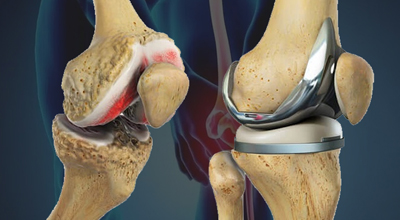

From emergency trauma management to elective procedures like knee replacement, arthroscopy, and spine surgery - our goal is to restore your mobility and improve your quality of life.